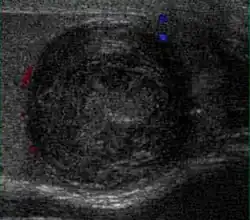

At ultrasound, the findings of acute epididymitis include an enlarged hypoechoic or hyperechoic (presumably secondary to hemorrhage) epididymis [Fig. 20a]. Other signs of inflammation such as increased vascularity, reactive hydrocele, pyocele and scrotal wall thickening may also be present. Testicular involvement is confirmed by the presence of testicular enlargement and an inhomogeneous echotexture. Hypervascularity on color Doppler images [Fig. 20b] is a well-established diagnostic criterion and may be the only imaging finding of epididymo-orchitis in some men.

At ultrasound, tuberculous epididymitis is characterized by an enlarged epididymis with variable echogenicity. The presence of calcification, caseation necrosis, granulomas and fibrosis can result in heterogeneous echogenicity [Fig. 21a]. The ultrasound findings of tuberculous orchitis are as follow: (a) diffusely enlarged heterogeneously hypoechoic testis (b) diffusely enlarged homogeneously hypoechoic testis (c) nodular enlarged heterogeneously hypoechoic testis and (d) presence of multiple small hypoechoic nodules in an enlarged testis [Fig. 21b].